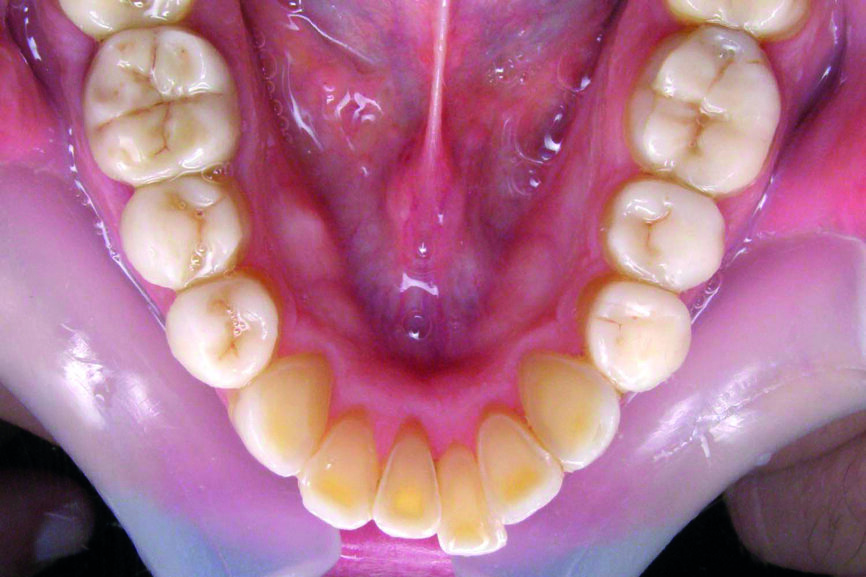

D’un point de vue dentaire le patient présente une Classe II division 1, avec une classe II molaire complète et une classe II canine.

- Présence d’un overjet et d’une supraclusion résiduelle.

- L’arcade supérieure est régulière mais les incisives sont en vestibulo version importante.

- L’arcade inférieure présente un encombrement dans le secteur antérieur associé à une version vestibulaire.

- Les milieux correspondent.